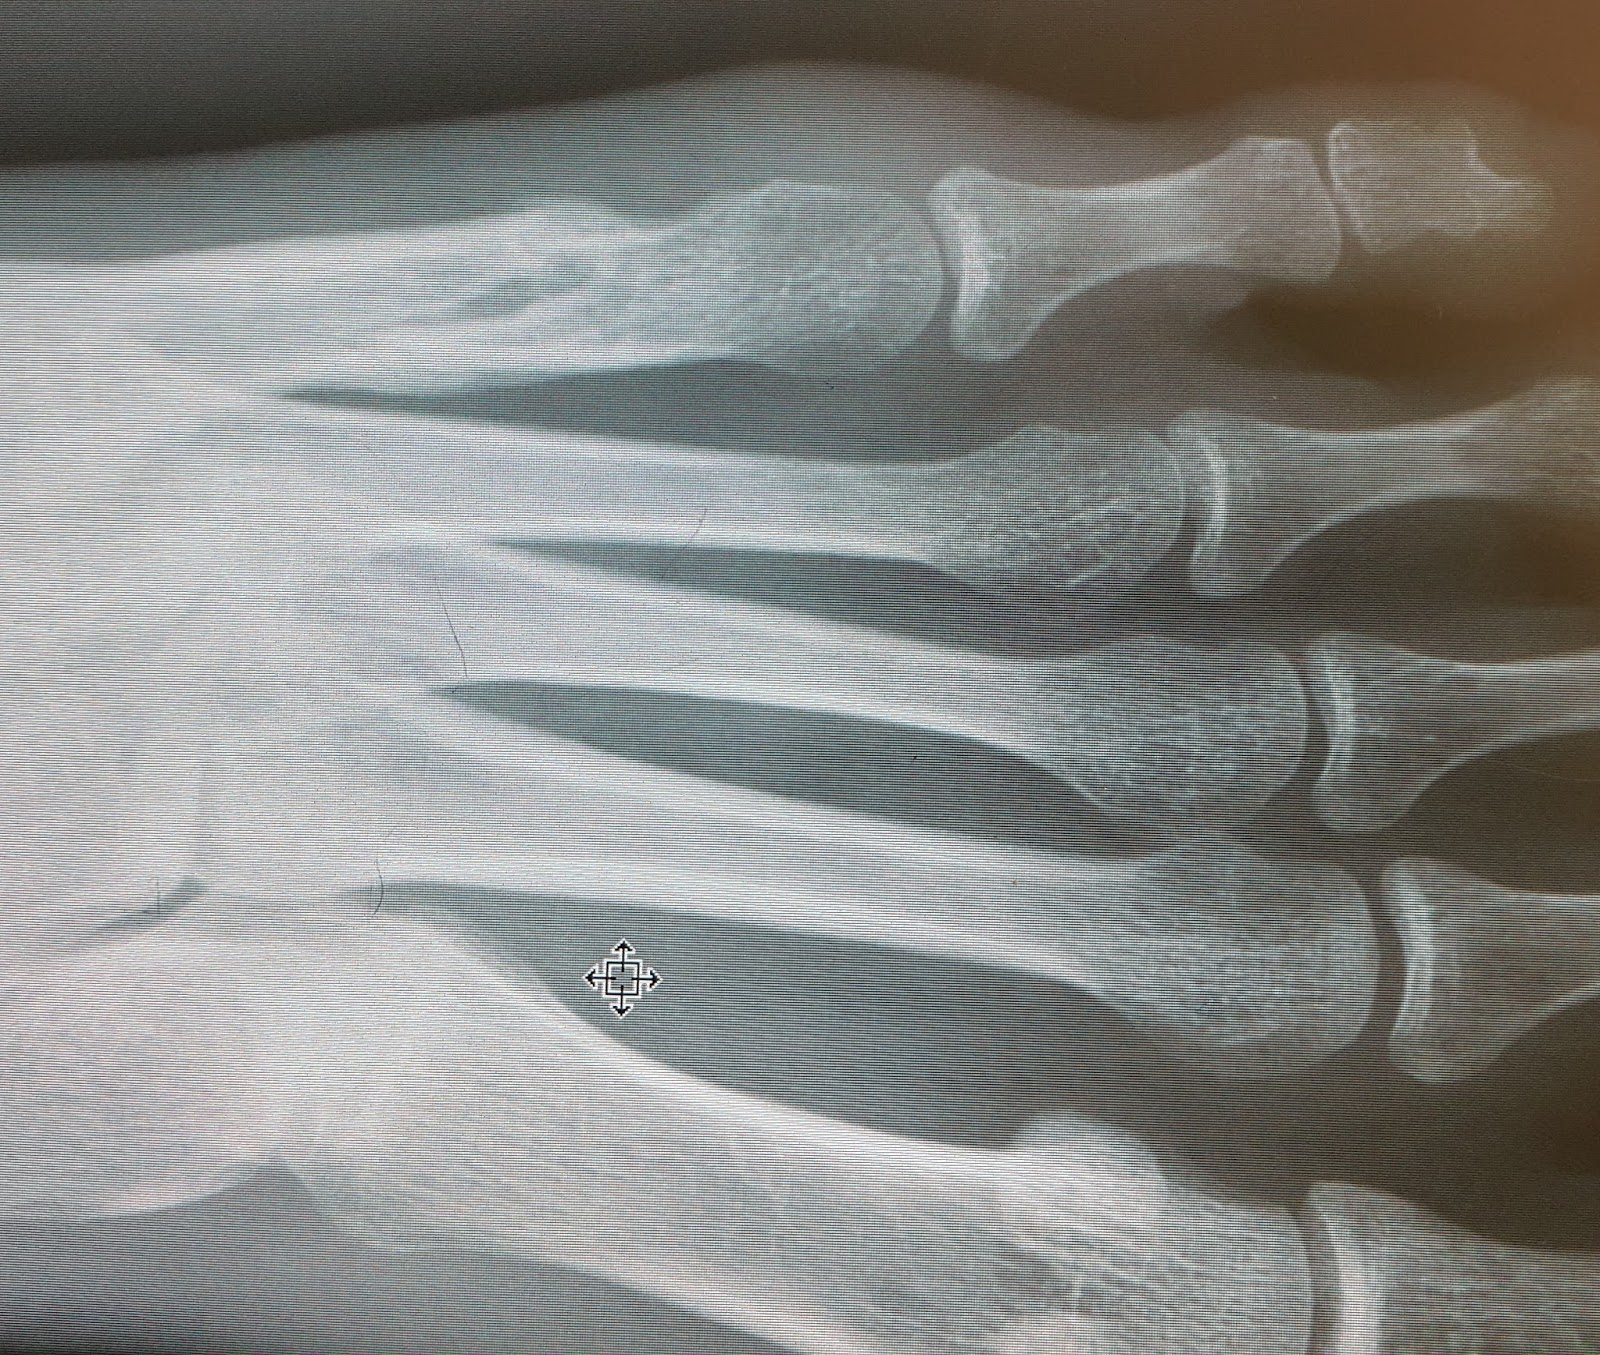

5th metatarsal fracture not healing jhBos Why Is My Bone Fracture Not Healing While your bone is healing, you can manage pain by resting the broken bone and taking medications as recommended by your healthcare provider. Learn more about delayed healing of fractures and some common risks for slow bone healing. the signs that a broken bone is healing are often typically an improvement in mobility and a decrease in pain. . Why Is My Bone Fracture Not Healing.